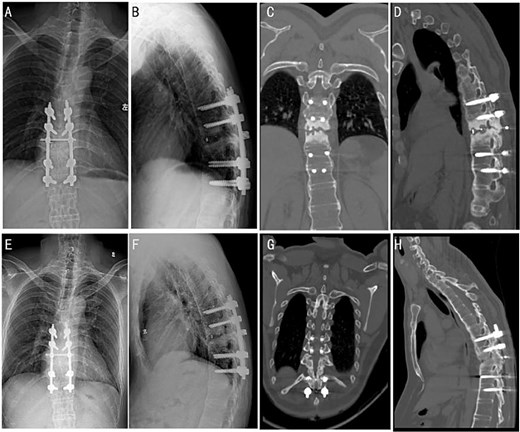

Surgical intervention was performed under general anesthesia. A posterior surgery approach from T8 to T12 was used under intraoperative C-arm fluoroscopy guidance. Pathological analysis of the intervertebral disc tissue confirmed the absence of inflammatory cell infiltration (Fig. 2A–C). Post-operative X-ray and CT imaging confirmed good alignment of the thoracic spine and stable internal fixation (Fig. 2D–I).

(A–C) Intraoperative pathology specimens obtained for further analysis. (D and E) Post-operative full-length spinal X-ray images. Typical post-operative Sagittal (F and G) and 3D CT reconstruction (H and I).

At a 4-month follow-up, an X-ray imaging confirmed the stable positioning of the instrumentation (Fig. 3A and B). The patient’s muscle strength demonstrated full recovery, with muscle strength in both lower limbs restored to Grade V. After 1 year, CT images showed evidence of bony fusion at the lesion site (Fig. 3C and D). After the 2 years follow-up, X-ray and CT images indicated solid bony fusion (Fig. 3E–H).

Post-operative follow-up images at different time periods. X-ray images were followed up 4 months after the surgery (A and B). CT images of patients were followed up 1 year after the surgery (C and D). X-ray (E and F) and CT (G and H) images were followed up 2 years after the surgery.